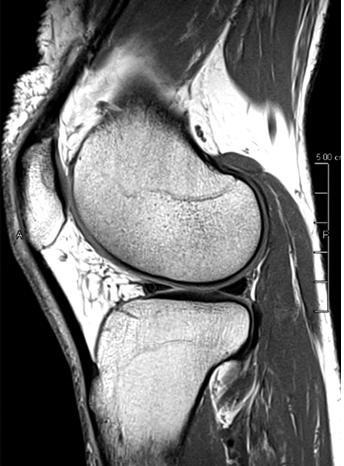

The power of MRI to pick up subtle injuries

Even the smallest injury in elite sports has implications. Having the right diagnostic tool at the peak of its development is vital to diagnosing subtle injuries that could impact player health. Using high resolution MRI therefore helps to identify very minute intra-articular joint injuries, muscle oedema changes or very small fibre tears (see fig 2).

Fig 2: Very small fibre tears identified using high resolution MRI